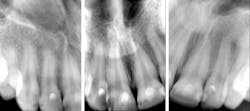

While her off-the-charts caries risk was the source of these problems, I don’t think resin composite did her any favors. Plaque loves composite and adheres to it much more tenaciously than it does enamel or amalgam. (1) Because of her esthetic demands, however, amalgam would have been a no-go.

Although it wasn't available at the time I treated Sydney, 3M’s Ketac Universal would have been a tremendous choice in her case. Ketac Universal would have given me a tooth-colored option that would not have attracted plaque, and ultimately recurrent decay, like resin composite did. The fluoride release and recharge would have been a handy weapon to have in the battle against Sydney’s caries.

I was taught in dental school that glass ionomers were not to be used on the occlusal surfaces of permanent teeth. For the majority of my career, I took that as dogma and never thought differently. Recent research on products in the same class as Ketac Universal has shown their tremendous success in Class I and II situations, with fracture rates similar to those of resin composites at recall visits up to six years after placement. (2) The high success rates of these new glass ionomers at six-year recall mean it's time to start reevaluating material choices when it comes to patients with high caries risk.

For a teenage patient like Sydney, would it have been better to use a glass ionomer material such as Ketac Universal, knowing that the restorations would at some point need to be replaced? In my mind, yes! My opinion is that the cycle of rerestoration for Sydney would have been slowed tremendously if I had used a product that had the excellent properties of traditional glass ionomers but with beefed-up wear and fracture resistance. It is not time to trash your resin composite. But it is my opinion—and I think the data backs this up—that the new generations of glass ionomer, such as Ketac Universal, deserve a spot on the shelf of every restorative dentist.